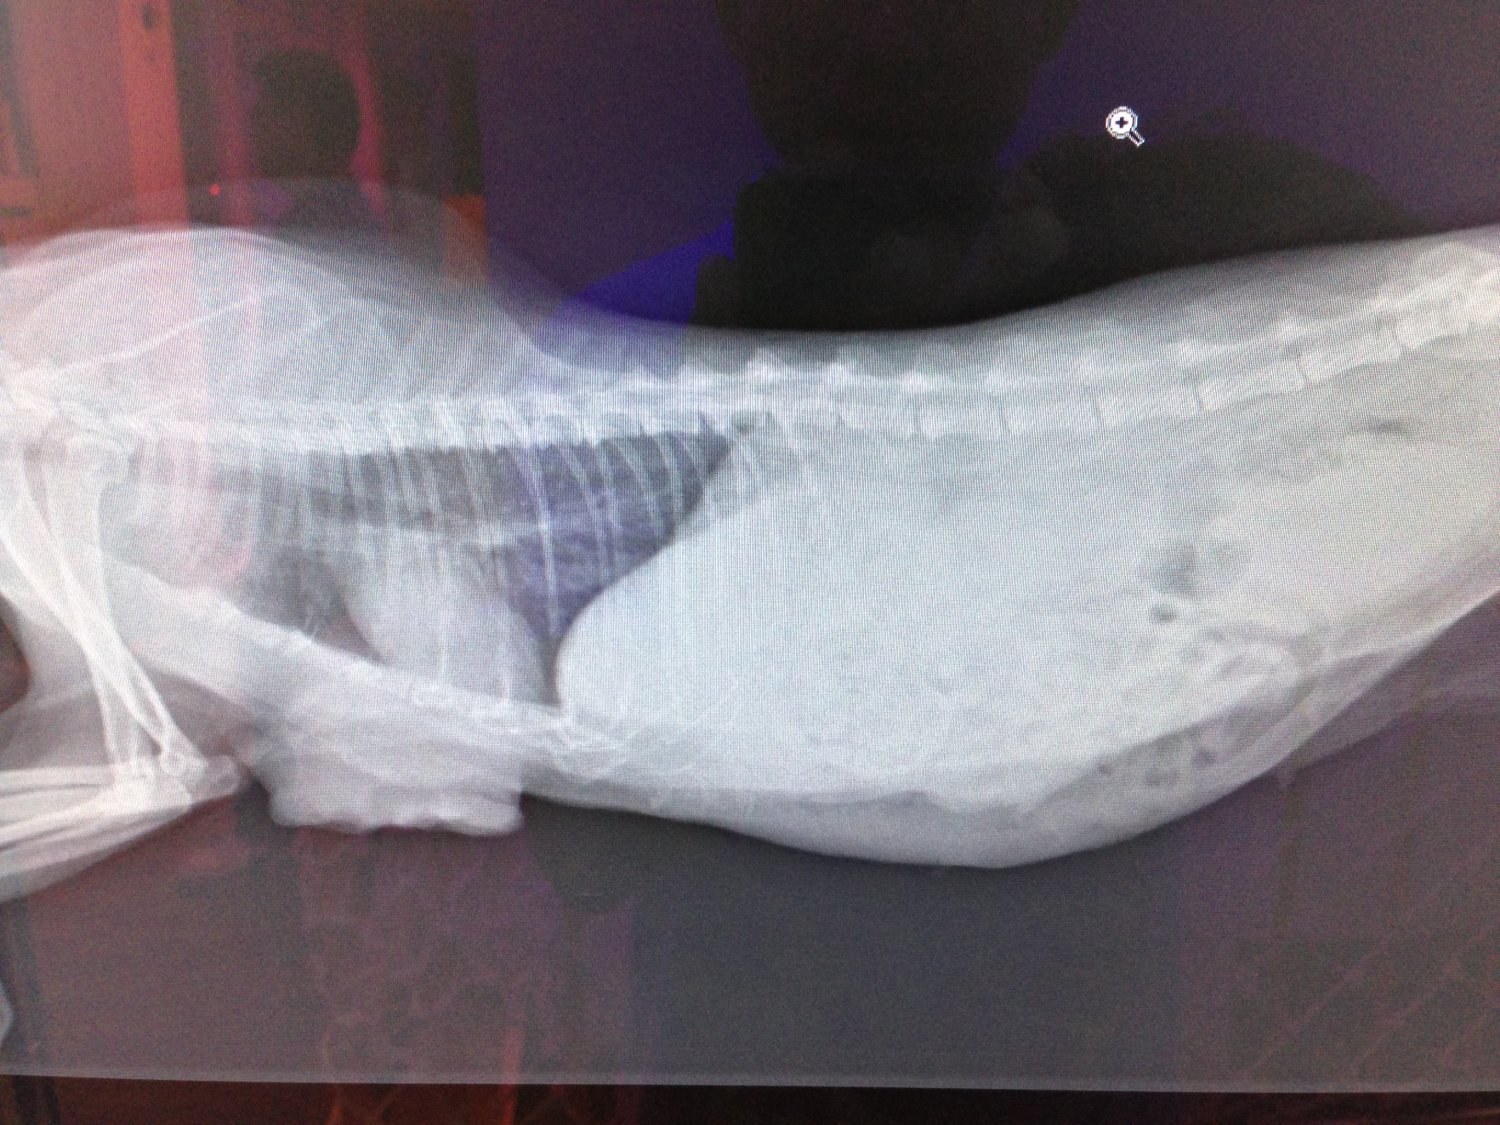

貓至醫院後,馬上安排檢查,發現不只乳腺腫瘤問題,腹腔也有疝氣及卵巢腫瘤,

一並給予手術切除及治療,在醫院休養了二個月,因腫瘤為惡性,有擴散現像,並

不適合再野放,通知志工,安排接出院安置後續照顧。